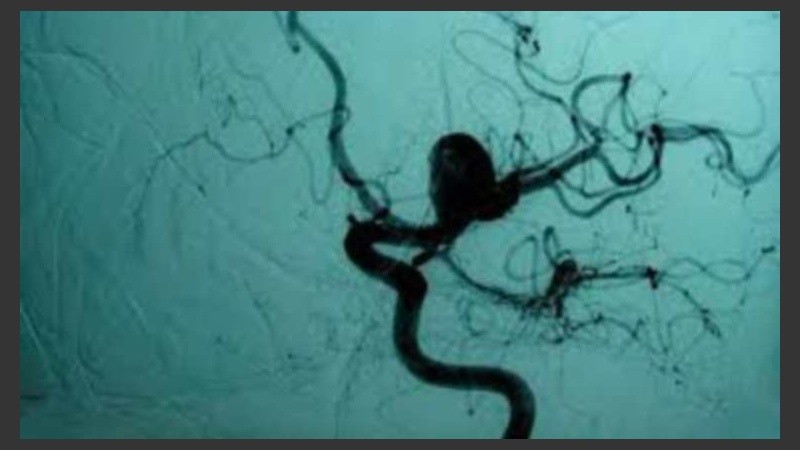

Cuando se produce un AC o debilidad en la pared de una arteria o vena del cerebro, una de las soluciones consiste en implantar un stent o segmento de malla metálica para asegurar una adecuada circulación sanguínea y evitar complicaciones (como rupturas) que pueden poner en riesgo la vida. Actualmente, el médico debe valerse de su experiencia para estimar la longitud y posición final del stent luego de ser insertado. Y la elección del dispositivo se realiza por medio de un par de medidas en proyecciones 2D de la anatomía del paciente, sin tener en cuenta gran parte de las irregularidades y variaciones del vaso.

La técnica ahora desarrollada está integrada dentro del software FVET (Fast Virtual Endovascular Treatment), que crea imágenes en 3D y facilita a los especialistas la planificación del procedimiento y la selección del dispositivo adecuado para el tratamiento preciso y seguro de ACs. “Permite determinar, antes de su colocación, en pocos segundos y con elevada exactitud, la longitud final que tendrá el stent en la estructura vascular”, afirmó Larrabide. También, ayuda a predecir su posición en el vaso y aneurisma tratado.